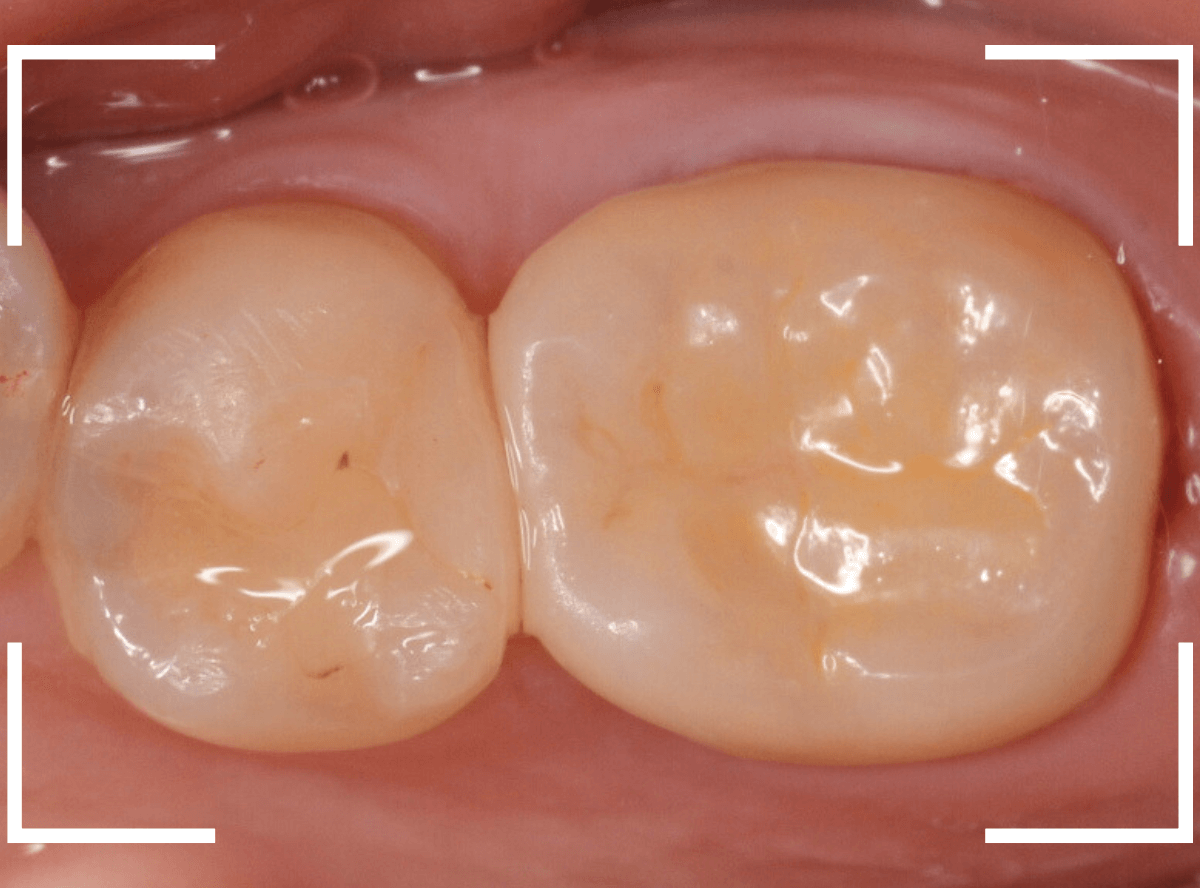

set後の写真です。

患者さんにも満足していただける仕上がりになりました。

治療前後の比較写真になります。